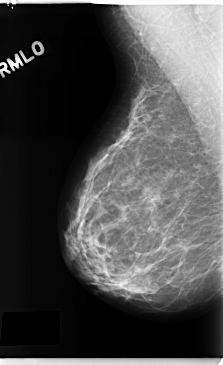

C_0271_1.RIGHT_CC

RIGHT_CC LINES 4712 PIXELS_PER_LINE 2568 BITS_PER_PIXEL 12 RESOLUTION 50 NON_OVERLAY